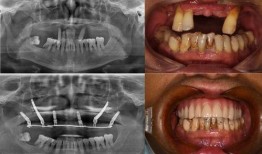

• 佛山种牙爆料事件视频曝光,揭露行业乱象引发关注

最近佛山那边的种牙事件可是闹得沸沸扬扬的,咱们得好好来聊聊这个话题。你有没有看过那个爆料视频?简直让人瞠目结舌啊!事件回顾:佛山...